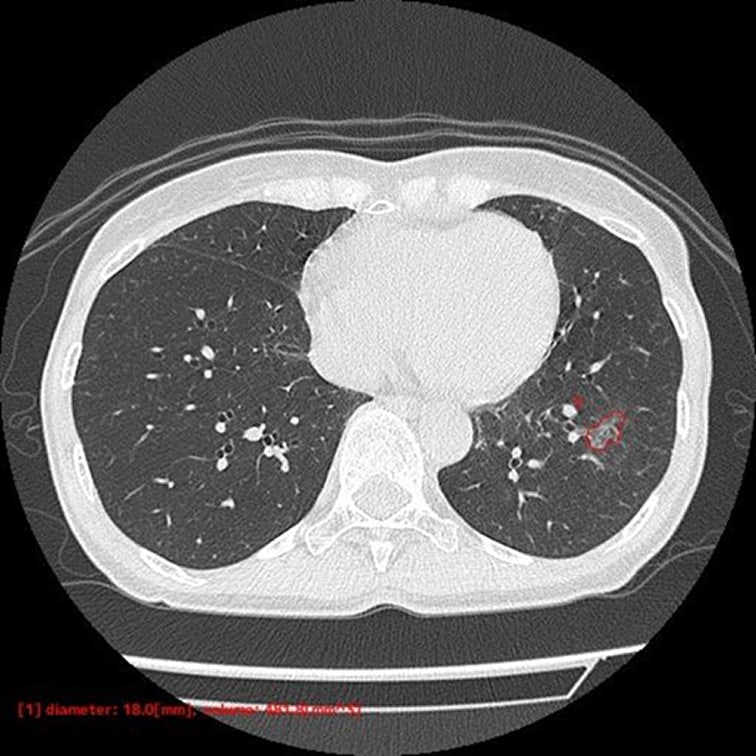

- 自動計測

- 検出した候補領域の大きさ:体積 [mm³] およびAxial断面最大径 [mm] を出力

- CT値:最大・最小・平均値・標準偏差を出力

低線量CT